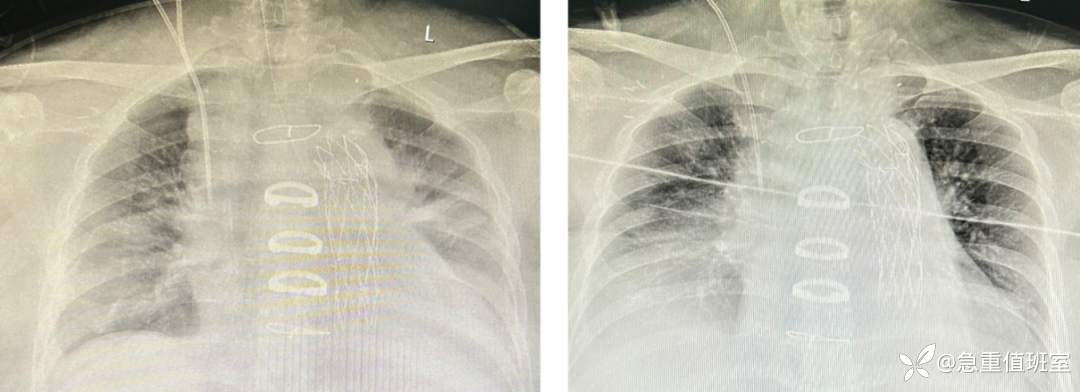

● 术后管理:术后患者预后良好,第二天拔管、撤除呼吸机,第四天转出 ICU。

图 6 患者术后胸片